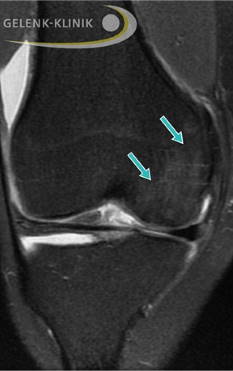

Nach der Behandlung mit einem OATS-Zylinder zeigt sich der Knorpel intakt und die Gelenkfläche wiederhergestellt. Der Knochen ist ebenso abgeheilt, das Ödem kaum noch nachweisbar. © Gelenk-Klinik

Außerdem ist die Transplantation technisch anspruchsvoll – der Spezialist muss den Zylinder exakt an die umliegende Knorpeloberfläche anpassen, damit keine Unebenheiten entstehen. Dieses Verfahren eignet sich besonders für kleinere Defektbereiche, welche mit 1–2 Zylindern behandelt werden können. Ein großer Vorteil ist die Versorgung des OD-Defekts im Kniegelenk durch körpereigenen funktionellen Knorpel. Das Knie ist nach dem Eingriff schnell wieder belastbar.